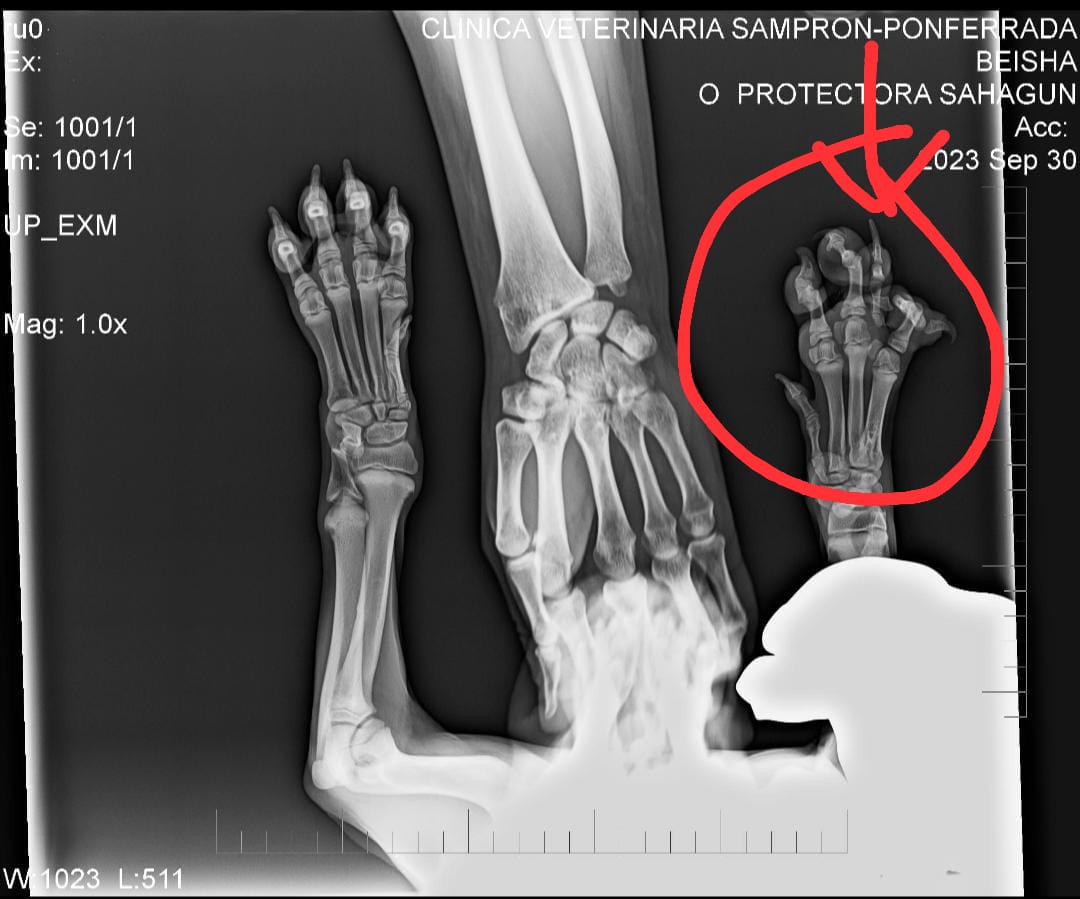

Bei Beisha wurde eine Fehlbildung in ihrer rechten Vorderpfote festgestellt. Ein Krallenbein ist nicht mit den Knochen verbunden. Der Tierarzt empfiehlt noch nicht zu operieren und die Entwicklung der Pfote sorgfältig zu beobachten. Im November diesen Jahres soll Beishas Pfote erneut untersucht und geröntgt werden.